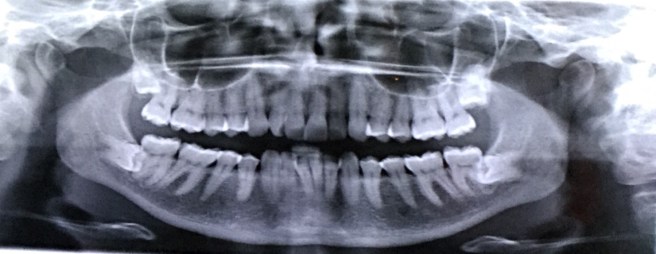

Here’s an awesome shot of those transgressing teeth. I told the kids we should print it out to use as a halloween decoration. (JUST JOKING!)

On a more serious note, the roots of these two teeth extend back around the nerve on either side of my jaw that controls feeling on my chin and lips. There is the possibility of damage, but apparently it’s just a feeling nerve, not related to motion in any way. I did pay the extra for a CT scan last week though so the surgeon could get a good look at how the roots are interacting with the nerves and can come up with a plan of attack before he cuts through my gum and bone.